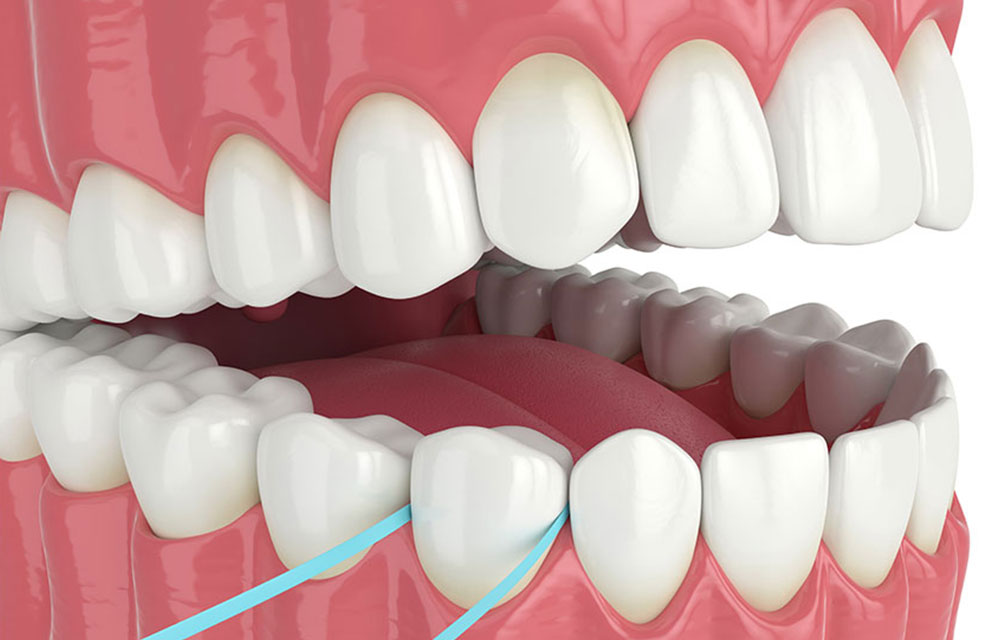

プラークコントロール

歯周病治療として最初に行うのが、歯周病の原因となるプラークや歯石の除去です。プラークや歯石を歯や歯ぐきのすき間に付着させないためには、ご自宅でのブラッシングによるプラークコントロールが重要になります。